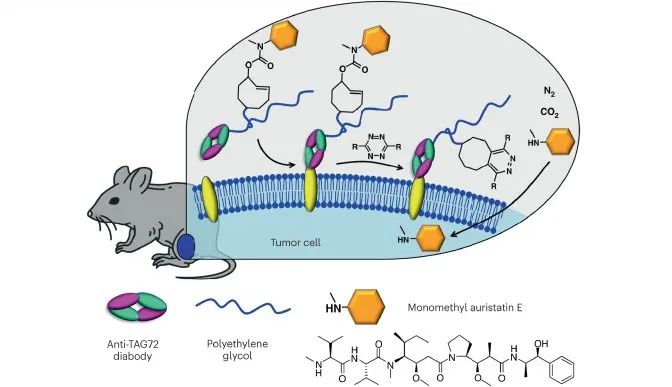

10.体内“点击化学”助力肿瘤靶向治疗

生物正交点击化学技术已在临床试验中应用于人体,帮助药物精准靶向肿瘤。点击化学疗法越来越受到大型制药公司的关注。点击化学能够将两个互补的分子通过化学反应像拼“乐高”玩具一样拼接在一起,由于这些分子只会跟特定的互补分子产生化学反应,它们可以在生物环境中进行化学反应而不影响到周围的其它分子。点击化学已经成为生物研究和药物发现中不可或缺的工具,该领域的先驱们因此获得了2022年的诺贝尔化学奖。

Tagworks在小鼠体内的MMAE递送,图片来源:Adapted from Rossin, R. et al.Nat. Commun.9, 1484 (2018).